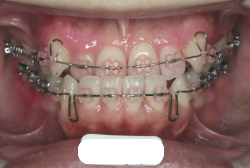

今回の患者様の場合は、「外科」も「小臼歯抜歯」も拒否されましたので、歯科矯正用アンカースクリュー(以下 アンカースクリュー)を用いて、下顎の歯列全体を後方に下げるという方法を取りました。

治療中の写真で、アンカースクリューより歯を後ろへ牽引しているのがお分かりいただけるかと思います。牽引を1年ほど続け、途中補助的に上下にゴムをかける(これを顎間ゴムと言います)手法なども追加し、全体で21ヶ月で治療を終えることが出来ました。

結局歯の本数を減らすことなく、すべてご自分の歯を残して、正しい配列と噛み合わせにすることができました。凸凹があまりひどくないため、簡単そうに見えると思いますが、このケースの初診の状態を見ると、熟練の矯正歯科医でも悩みのつきないケースです。まして、外科も出来ない、抜歯もイヤ、と言うことになると、従来の方法では治療不可能と考えられるのですが、アンカースクリューを使うことで最近は不可能が可能となってきました。